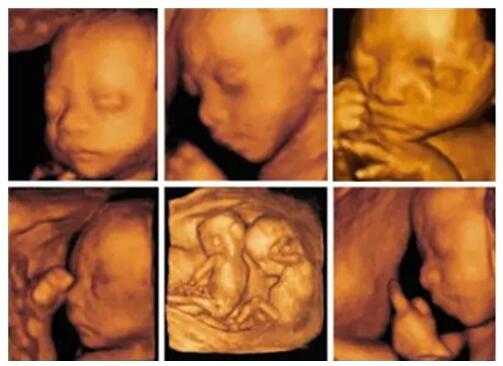

晒娃这件事, 当然得从娘胎开始 刚刚做了四维视频 你是否也想炫一把 但你 还只是发了个微博或朋友圈 然后转发给了几个亲朋戚友 就一直放在电脑上 自己默默地观赏 你 out啦 其实,...这么酷炫的四维视频,让你分分钟变身朋友圈的网红宝宝~ 2017-08-07